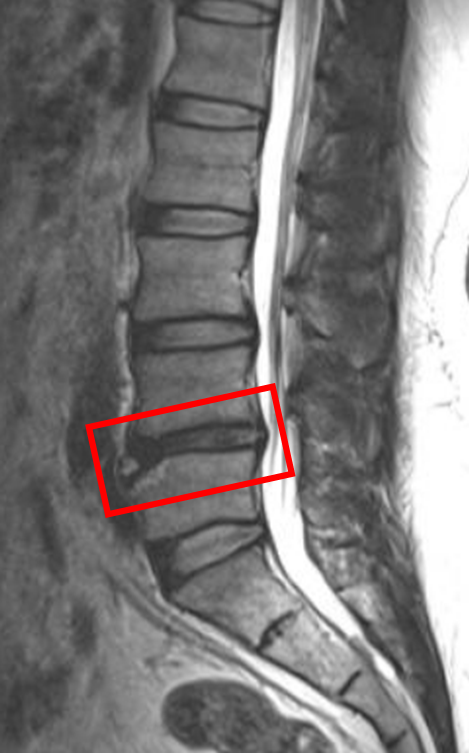

【治療経過のご紹介 No.197】L4/5の椎間板変性の患者様

この患者様は赤い枠で示されている箇所(L4/5)に椎間板変性を認めます。